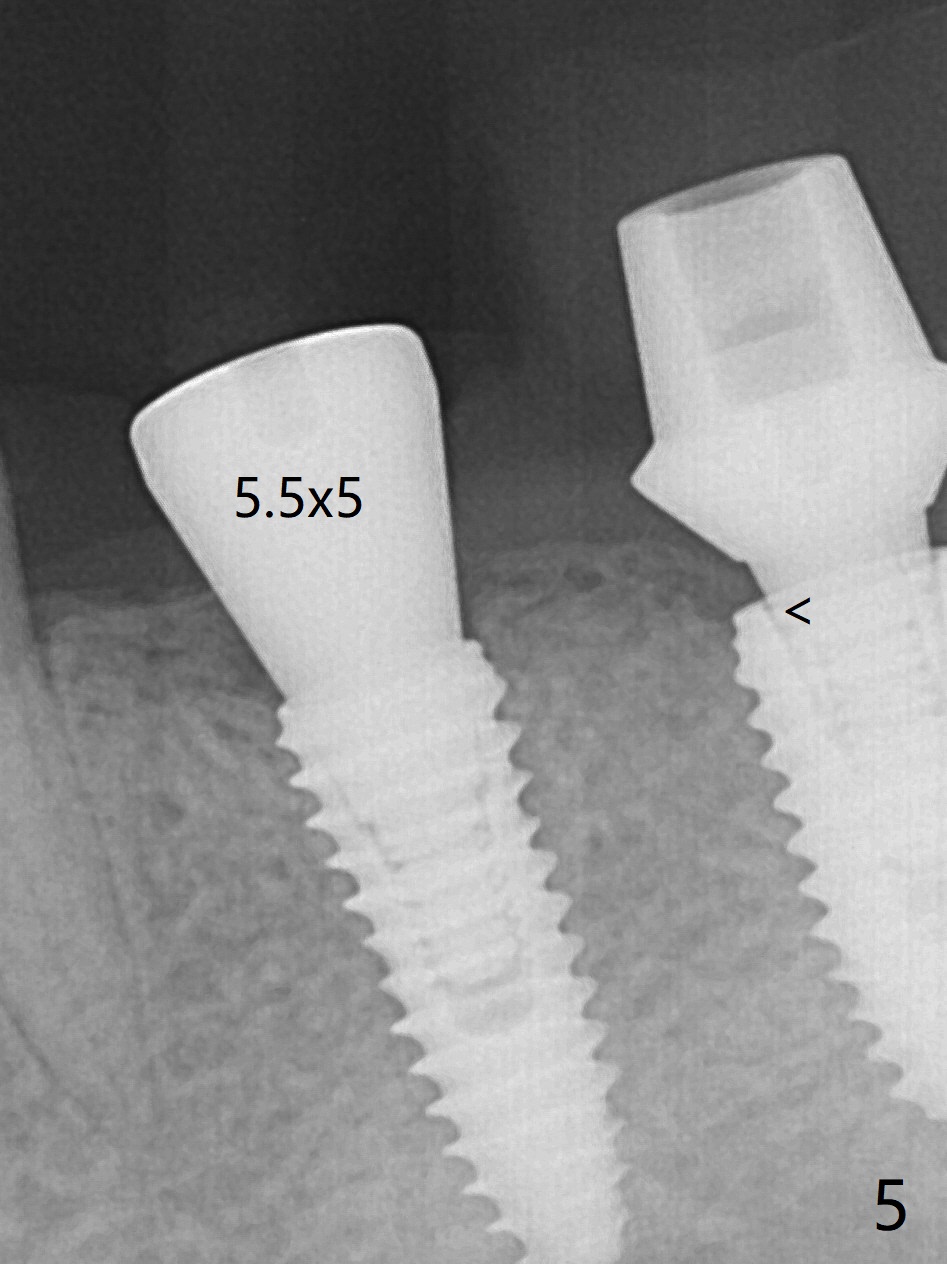

Socket Shield is conducted at #20 (Fig.1-3 *). With placement of a 4x11.5 mm implant equicrestal lingually, a 4.5x6(2) mm temporary abutment is unable to be seated incompletely (Fig.4 black <) because of proximal crestal interference (white arrowheads). After use of a 5.5 mm profile drill, a 5.5x5 mm healing abutment is apparently seated completely (Fig.5). Upon close look, the abutment at #19 is also incompletely seated. In fact #18/19 temporary crowns and #19 abutment are loose. A 6.8x4 mm healing abutment is later placed at #19. Periodontal dressing is applied at #18-20. In fact buccolingual control of osteotomy is not easy with free hand. A smaller implant (e.g., 3.5 mm) may be easier.